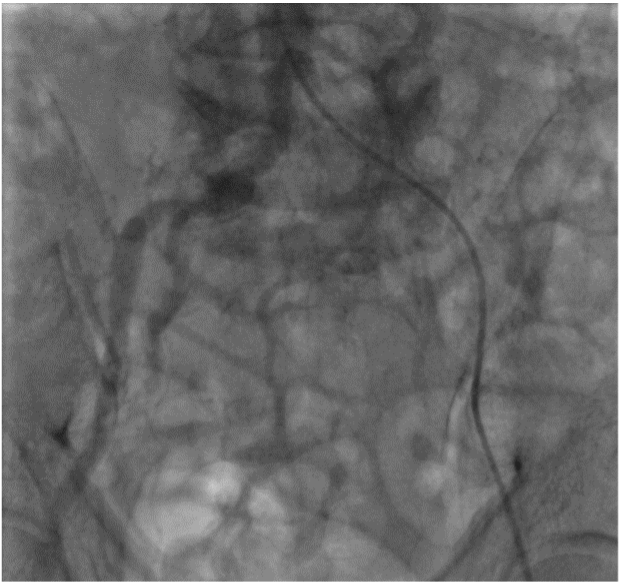

Hệ thống mạch máu chi dưới của bệnh nhân được dựng hình

Chụp mạch dưới DSA cho thấy dấu hiệu tắc động mạch chậu trái

Khi thăm khám lâm sàng, bác sĩ ghi nhận động mạch đùi, động mạch khoeo và động mạch dưới gối chân bên trái không bắt được, loét gót chân trái. Kết quả siêu âm Doppler mạch máu chi dưới ghi nhận tắc động mạch chậu bên trái, mất phổ 03 pha động mạch đùi, khoeo chân trái. Bệnh nhân được chụp cắt lớp vi tính mạch máu chi dưới (CTA) để đánh giá cụ thể và chính xác hơn tình trạng bệnh lý của mạch máu.

Kết quả CTA cho thấy tắc động mạch chậu bên trái, tắc 1/3 giữa động mạch đùi bên trái và xơ vữa rải rác các động mạch chi dưới khác. Trước tình trạng tổn thương phức tạp này, các bác sĩ chỉ định can thiệp nội mạch (Endovascular Intervention) để kịp thời tái thông các mạch máu bị tắc gồm động mạch chậu và động mạch đùi nông bên trái.